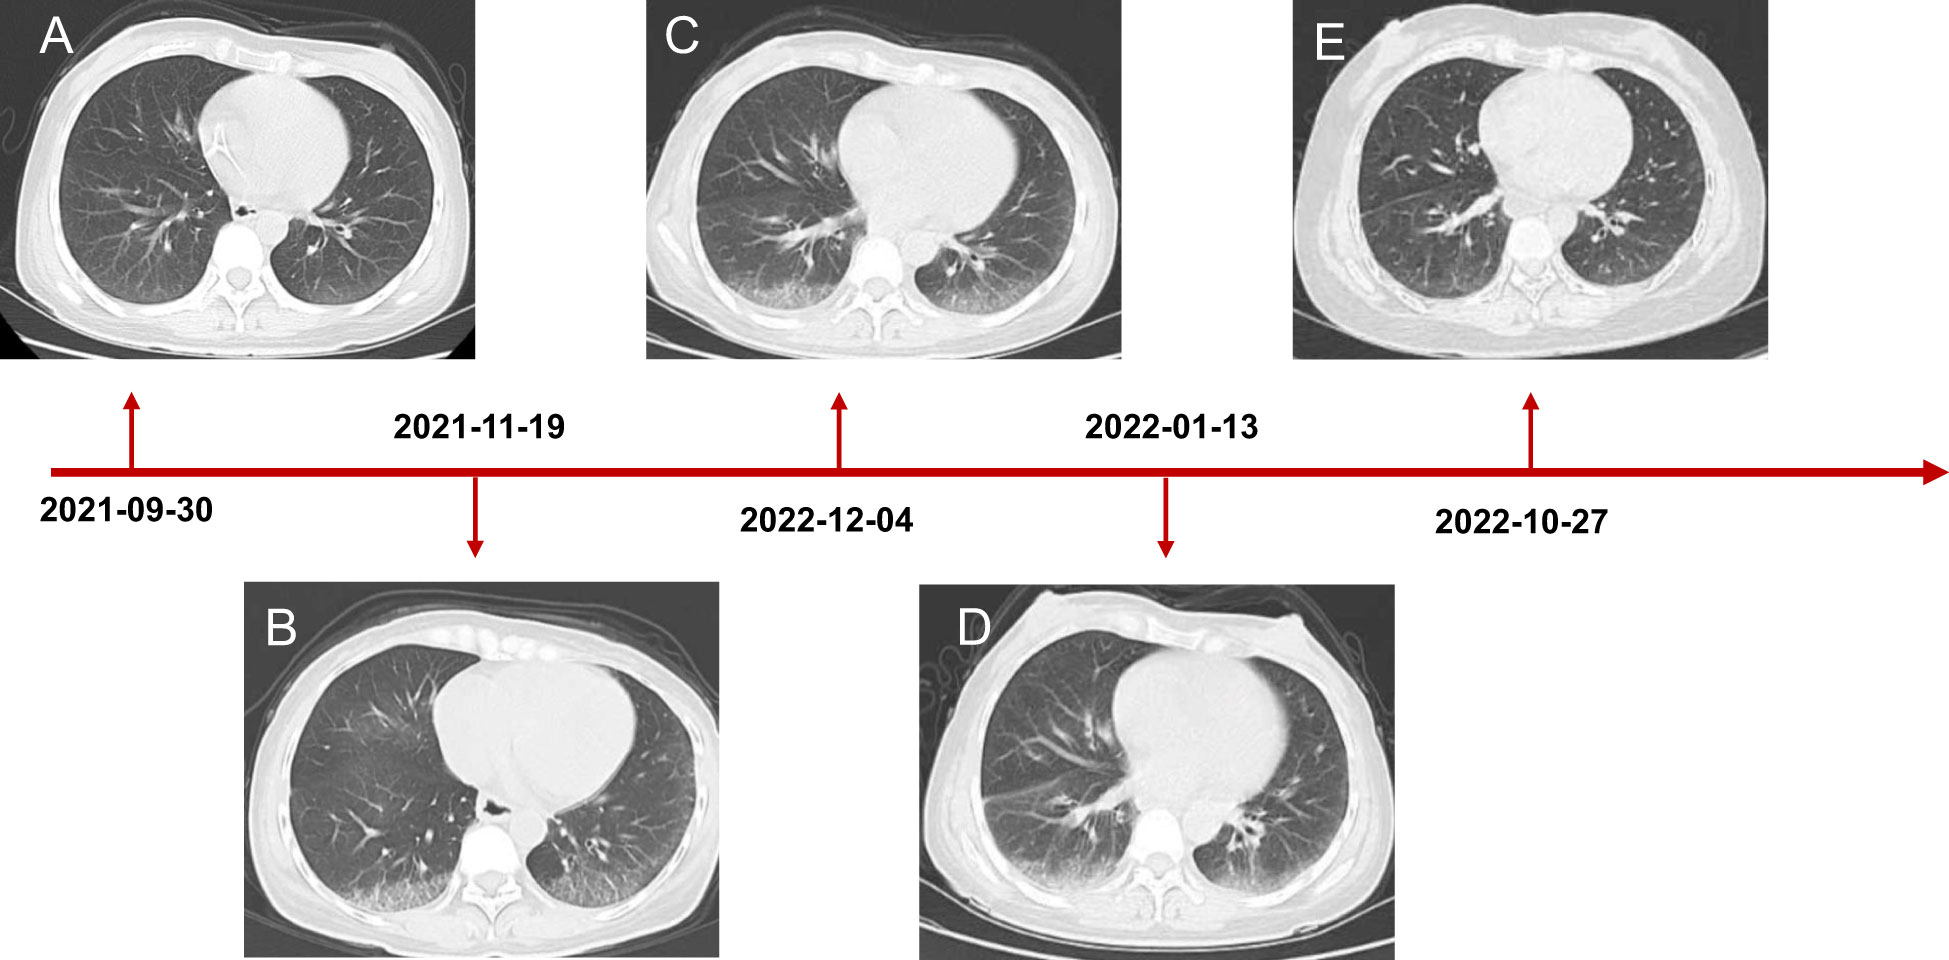

Coloscopy was performed, and pathological analysis of the tumor revealed adenocarcinoma (Figures 1C, D). Immunohistochemistry showed positivity for MLH1, MSH2, and MSH6 and negativity for PMS2. Next-generation sequencing confirmed that the tumor was MSH-H. However, the patient refused immunotherapy. Thus, a first cycle of chemotherapy consisting of mFOLFOX6 plus bevacizumab was administered on 1 October 2021. After three cycles, an abdominal CT scan showed an impressive reduction in tumor size in the right colon, while the retroperitoneal lesion remained stable. A chest CT revealed interstitial pneumonia (Figure 2), but the patient did not experience dyspnea. A multidisciplinary team (MDT) discussion, including surgical staff, was organized to formulate further treatment plans. Specialists recommended pembrolizumab, nivolumab, or nivolumab in combination with ipilimumab—all approved therapies for patients with metastatic MSI-H/dMMR colon cancer regardless of their eligibility for intensive therapy. Since the patient could not afford the expenses of the recommended courses of treatment, envafolimab was suggested instead. With patient and treatment teams reaching an agreement, the patient was started on envafolimab (150 mg, administered subcutaneously, once weekly) on 21 September 2021. Interstitial pneumonia did not worsen over the course of treatment, as evidenced by chest CTs. One month later, the patient experienced pain in her extremities with elevated creatine kinase (CK) and creatine kinase isoenzyme MB (CK-MB) levels. No significant laboratory findings involving cardiac troponins or N-terminal pro-brain natriuretic peptide were observed. We consulted cardiologists in our hospital. who excluded the possibility of ICI-related myocarditis but suspected myositis. However, she refused a proposal of muscle biopsy. According to the Management of Immune Checkpoint Inhibitor-Related Toxicity section of the Guidelines of the Chinese Society of Clinical Oncology, the symptom is classified in Grade 1, for which dose reduction or discontinuation are not considered. Therefore, nonsteroidal anti-inflammatory drugs (NSAIDs) and low-dose methylprednisolone (12 mg daily) were administered, and immunotherapy was continued. Decreased CK and CK-MB were observed three days after management (Figure 3). On 1 March 2022, a CT scan showed a decrease in volume, prompting a second MDT to suggest the patient continue treatment. A greater reduction in lesion size was observed during a follow-up CT scan in May 2022. Moreover, envafolimab with methylprednisolone (4 mg, daily) was well tolerated. Thirty-six cycles later, the lesion in the right colon disappeared on an abdominal CT scan performed on 18 August 2022 (Figure 4). Post-treatment colonoscopy revealed no neoplasm, and immunohistochemistry revealed chronic mucositis (Figures 1E, F). PET/CT also showed that the patient achieved CR efficacy (Figure 1B). Given the safety of envafolimab, the patient was started on 400 mg of envafolimab every 3 weeks without additional adverse events. CK and CK-MB levels remained low.

Figure 3 Chest CT scanning of the patient. (A) CT showed lung status without disease before treatment initiation. (B) The patient developed interstitial pneumonia after three cycles of mFOLFOX6 and bevacizumab. (C) CT demonstrated lung injury did not progress after five cycles of chemotherapy and targeted therapy. (D) Interstitial lung disease still existed but did not worsen after two cycles of envafolimab. (E) The lung disorder even reversed after the patient challenged envafolimab 400mg every three weeks.

In this case, our patient developed interstitial pneumonia after two cycles of mFOLFOX6 and bevacizumab. While the component causing pulmonary toxicity was unknown, a few reports have found bevacizumab and leucovorin to cause lung damage (15, 16). Conversely, oxaliplatin may have been the toxic agent, as the pulmonary disease did not recur with oxaliplatin-free chemotherapy but did with 5FU and leucovorin (17, 18). Though pulmonary toxicity from FOLFOX is uncommon, it could be lethal despite the discontinuation of the agents and the initiation of immunotherapy. Considering the reasonable safety of envafolimab, with no immune-related pneumonitis in its phase 2 study, it was used to treat the patient (3). Fortunately, the interstitial pneumonia did not worsen. Our patient was administered a subcutaneous injection of 300 mg Q3W when CK and CK-MB trended toward stability. Moreover, the fixed-dose schedule prevented additional adverse events and proved efficacious and convenient. Notably, the patient also developed immunotherapy-induced myositis, a rare condition typically only seen in a case series. While immune-related myositis was not observed in the envafolimab clinical trial, it has been reported as a complication of other ICIs. Among 9,088 patients receiving ICIs at the MD Anderson Cancer Center, 0.4% were diagnosed with ICI-myositis, 0.94% with combination ICI therapy, and 0.31% with ICI monotherapy. The delay between ICI initiation and myositis onset was approximately one month. Moreover, the onset of myalgia during ICI-myositis was quicker than that in primary autoimmune polymyositis (19). Reported symptoms characteristic of ICI-myositis include myalgia, limb-girdle weakness, and oculomotor weakness with diplopia (20). The outcomes of patients with only elevated CK, including those who needed short hospitalizations for CK normalization, were more favorable than those of patients with overlapping syndromes (21). Further studies are needed to clarify the mechanism of ICI-myositis, the biomarkers to predict, and the time to rechallenge ICIs.